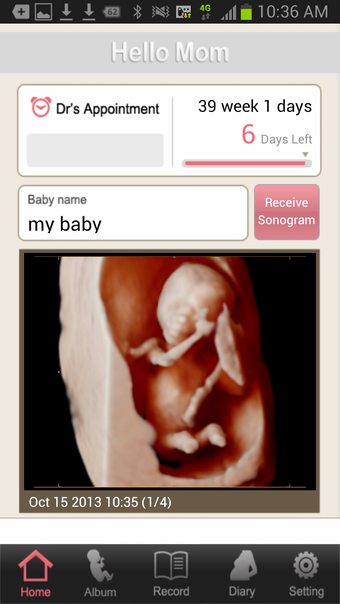

Ultrasound diary

1) Browse Sonogram on a mobile device

- You can view ultrasound images you have received from a Samsung Medison ultrasound system on your device.

- You can also view an image of your baby or a part of your baby's body (if it was saved to your device) from your ultrasound system at your hospital